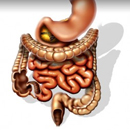

Po e fillojme pastrimin pas dhembeve me zorren e trashe. Ajo eshte 1 m , 30 cm dhe diameter 7-8cm. Pastrimi i zorres se trashe eshte nje veprim i rendesishem per shendetin e njeriut. Ajo duhet te behet menjehere duke e vendosur seriozisht per ta bere kete veprim. Zorra nuk mund te pastrohet dot vete, as ushqimet nuk e favorizojne kete. Duke patur nje zorre te bllokuar ajo eshte shkaktare kryesore per shume semundje si dhe shkaktare per mosthithjen e vitaminave, proteinave dhe kriprave minerale, nga ushqimet qe ne hame. Me pastrimin e zorres trupi do te kete me shume energjidhe vitalitet. Pasi zorra te jete liruar nga papastertite kalohet ne fazene dyte qe eshte heqja dore nga zakonet e ngrenies dhe te pirjes se ushqimeve qe bllokojne zorren. Mund tu duhen muaj dhe vite qe te rregullohet shendeti juaj, sepse muaj dhe vite kane qene ato qe ju keni abuzuar me trupin tuaj. Kur do te jete arritur nje eleminm korrekt i papastertive te zorres, jemi ne gjysem te rruges, pjesa tjeter! eshte rindertimi i indeve qe jane demtuar me pare. Patrimi i zorres behet per te rregulluar ne menyre efikase punimin e zorres. Ne nje prej tregimive te mjekeve te autopsise tregohet se nje person pasi i eshte bere autopsia zorra e trashe e tij ka patur 18 kg mbeturina te cilat i ka mbajtur ne barkun e ti ngado qe ka shkuar. Ndersa nje moter muslimane pasi ka pastruar zorren e saj per disa dite ka rene 5 kg ne peshe. Pse?Keshtu edhe me keq 18 kg.

Dr.Xhon Harvi Kellog ishte ne dijeni te shume rasteve te disa lloj operacionesh qe ishin evituar me pastrimin dhe vitalitetin e zorres. Ai ishte i bindur qe perqindja e semundjeve te vendeve te civilizuara te botes jane pre deficences se zorre. Demonstrimet midis zorres dhe semundjeve nuk le asnje dyshim qe intoksikimi i trupit dhe shkaku i shume semundjeve vjen prej zorres se trashe. Pjesa e fundit e zorres ka nje dimension te tille qe kerkon nje zbrazje te saj cdo 6 ore. Por si shkak i zakoneve tona mbajme kete papasterti per 24 ore, rezultati :ulcer dhe kancer. Nje zorre e paster jep nje shendet te mire. Apandesiti, infeksioni i bajameve, ne melci , ne temth, disfunksionet kardiake dhe te eneve te gjakut, arteriet, sinoziti, reumatizma etj, pa asnje dyshim kane origjine ne nje zorre pertace qe nuk funksionon sic duhet. Duhet te na bejne te mendojme numri i madh i operacioneve te fistulave, homorroideve shqetesimet e prostates i tumoreve etj. Pjesa me e madhe e njerezve ! gjate femijerise nuk kane qene edukuar qe ta kuptojne rendesine e nje nxjerrje te duhur te perditshme. Zorra e trashe eshte organi kryesor qe duhet te mbahet paster dhe format e pastrimit te zorres se trashe do ti trajtojme pas ketij shkrimi.

Duke pare rendesine e madhe te pastrimit te kolonit nga papastertite dhe mbetjet po tregojne disa menyra te pastrimit te zorres se trashe.